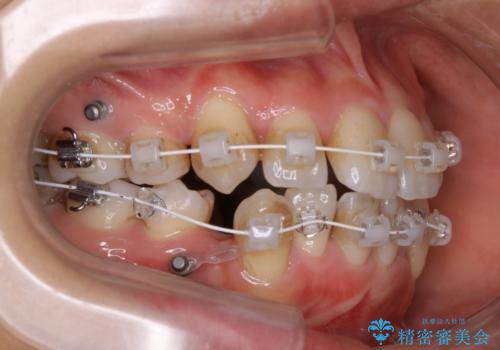

- 矯正装置

- ワイヤー(審美装置)

- 1年6ヶ月

- 10-30回

- 審美装置/93万円(税込み) マイクロインプラント4本/8.8万円(税込み)費用は治療当時の料金となります